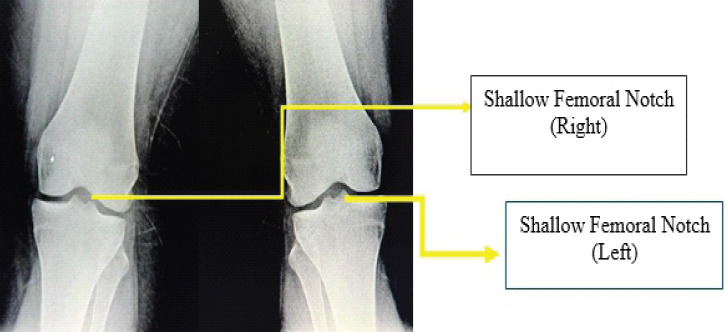

Case report: We herein report a case of bilateral isolated congenital absence of ACL in a 24-year-old young woman who presented to us with the chief complaints of pain in the right knee for the past 2 years and the left knee for the past 10 months.